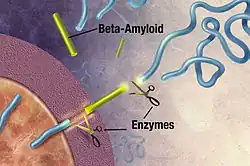

Alzheimer's disease is an incurable neurodegenerative disease which most often affects the elderly and accounts for more than half of all cases of dementia. Its exact cause remains unknown, but the disease is identified as a protein misfolding disease. Alzheimer's is associated with toxic aggregations of the amyloid beta (Aβ) peptide, caused by Aβ misfolding and clumping together with other Aβ peptides. These Aβ aggregates then grow into significantly larger senile plaques, a pathological marker of Alzheimer's disease.[49][50][51] Due to the heterogeneous nature of these aggregates, experimental methods such as X-ray crystallography and nuclear magnetic resonance (NMR) have had difficulty characterizing their structures. Moreover, atomic simulations of Aβ aggregation are highly demanding computationally due to their size and complexity.[52][53]

Preventing Aβ aggregation is a promising method to developing therapeutic drugs for Alzheimer's disease, according to Naeem and Fazili in a literature review article.[54] In 2008, Folding@home simulated the dynamics of Aβ aggregation in atomic detail over timescales of the order of tens of seconds. Prior studies were only able to simulate about 10 microseconds. Folding@home was able to simulate Aβ folding for six orders of magnitude longer than formerly possible. Researchers used the results of this study to identify a beta hairpin that was a major source of molecular interactions within the structure.[55] The study helped prepare the Pande lab for future aggregation studies and for further research to find a small peptide which may stabilize the aggregation process.[52]

In December 2008, Folding@home found several small drug candidates which appear to inhibit the toxicity of Aβ aggregates.[56] In 2010, in close cooperation with the Center for Protein Folding Machinery, these drug leads began to be tested on biological tissue.[35] In 2011, Folding@home completed simulations of several mutations of Aβ that appear to stabilize the aggregate formation, which could aid in the development of therapeutic drug therapies for the disease and greatly assist with experimental nuclear magnetic resonance spectroscopy studies of Aβ oligomers.[53][57] Later that year, Folding@home began simulations of various Aβ fragments to determine how various natural enzymes affect the structure and folding of Aβ.[58][59]